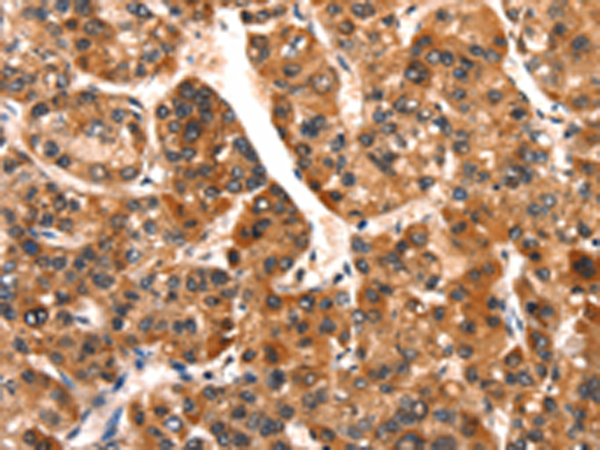

分类: 科研抗体货号: P11213别名: KPM应用: IHC反应种属: Human, Mouse